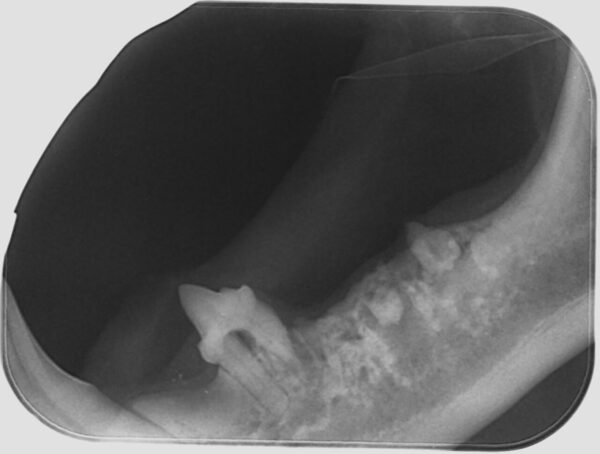

- Técnica en bisectriz: para evaluar el resto de los dientes. El captador se coloca lo más paralelo posible a la raíz del diente y, a continuación, se halla el ángulo entre la raíz del diente y el captador. Este ángulo se corta por la mitad (bisectriz) y el haz de rayos se dirige perpendicular a esta (imagen 4).